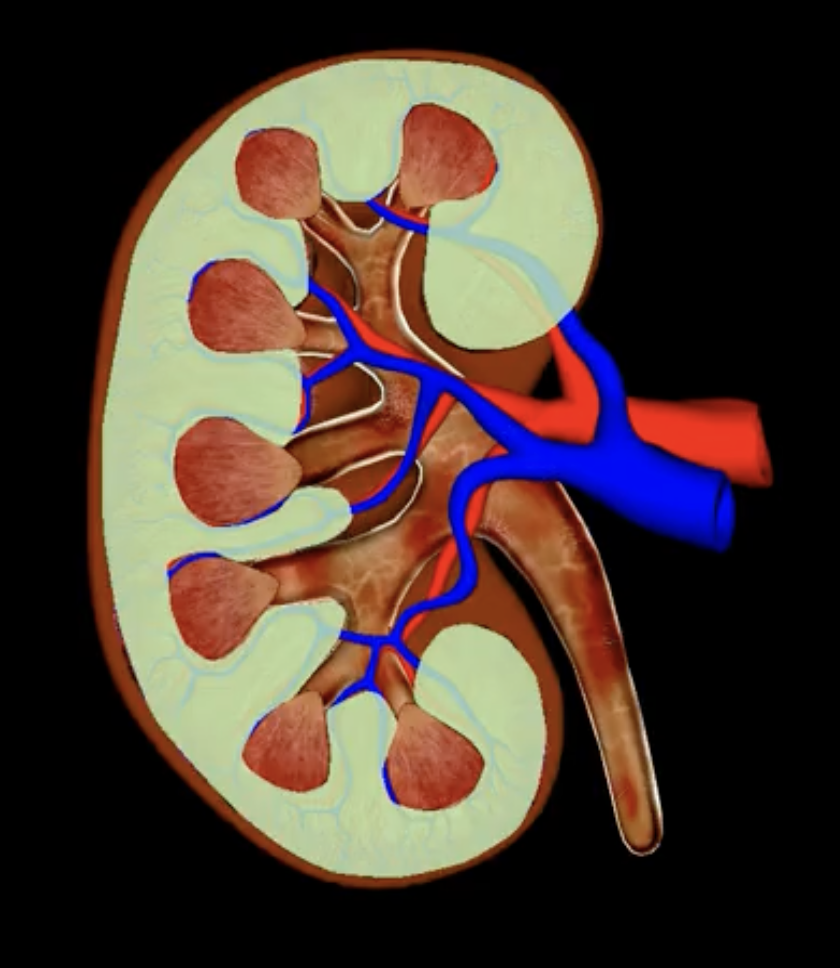

renal cortex

green

renal medulla

blue

renal columns

yellow

renal pyramids

purple

renal lobe

orange

renal papilla

minor calyx

teal

major calyces

renal pelvis